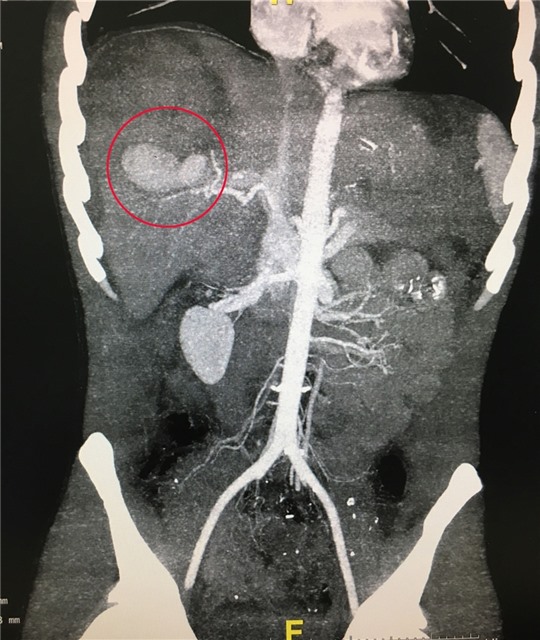

Các bác sĩ Bệnh viện Việt Nam - Thụy Điển Uông Bí vừa cấp cứu cho một trường hợp bị vỡ gan bằng kỹ thuật nút động mạch gan. Đây là một trong những kĩ...